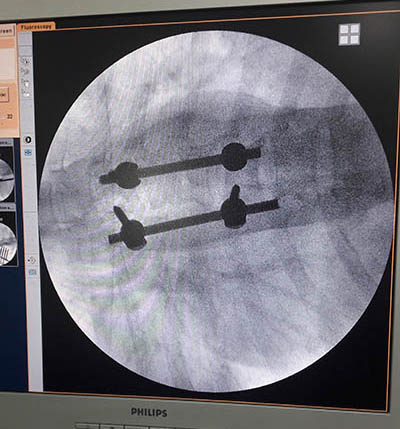

He has treated numerous complex spine ailments like metastatic tumors, osteoporotic fractures (vertebroplasty), degenerative diseases and listhesis etc.